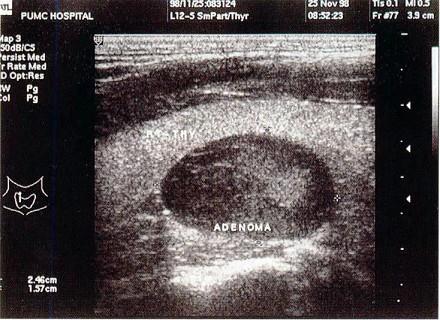

患者颈部包块5年,结合超声声像图,最可能的诊断是?(?)A.甲状腺瘤B.甲状腺癌C.甲状腺结节D.甲状腺炎E.桥本氏甲状腺炎

问题 患者颈部包块5年,结合超声声像图,最可能的诊断是?(?)

选项 A.甲状腺瘤 B.甲状腺癌 C.甲状腺结节 D.甲状腺炎 E.桥本氏甲状腺炎

答案 A